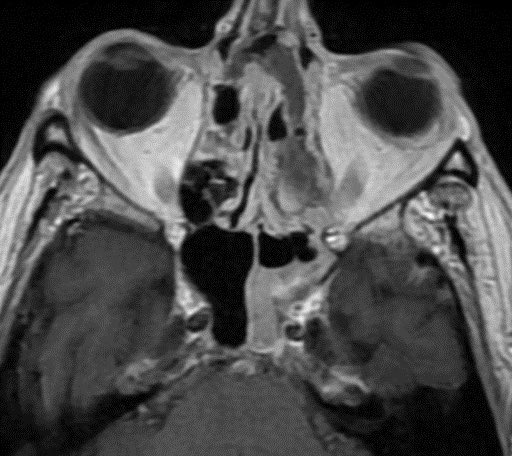

60 y/o with history of diabetes presents with progressive right proptosis, vision loss and confusion. What is the most likely diagnosis? 🧠

💡 Black Turbinate Sign has been reported as a finding highly suggestive of invasive fungal rhinosinusitis in immunocompromised patients

💡 Absent sinus mucosal enhancement is a 🔑 imaging feature as it implies invasion with vascular compromise and necrosis of the mucosa

The black turbinate sign is very specific in the appropriate setting though often not seen

💡 We must look for extra sinus invasion, particular intracranially, intraorbital, retromaxillary and other areas of absent mucosal enhancement to aid in the diagnosis